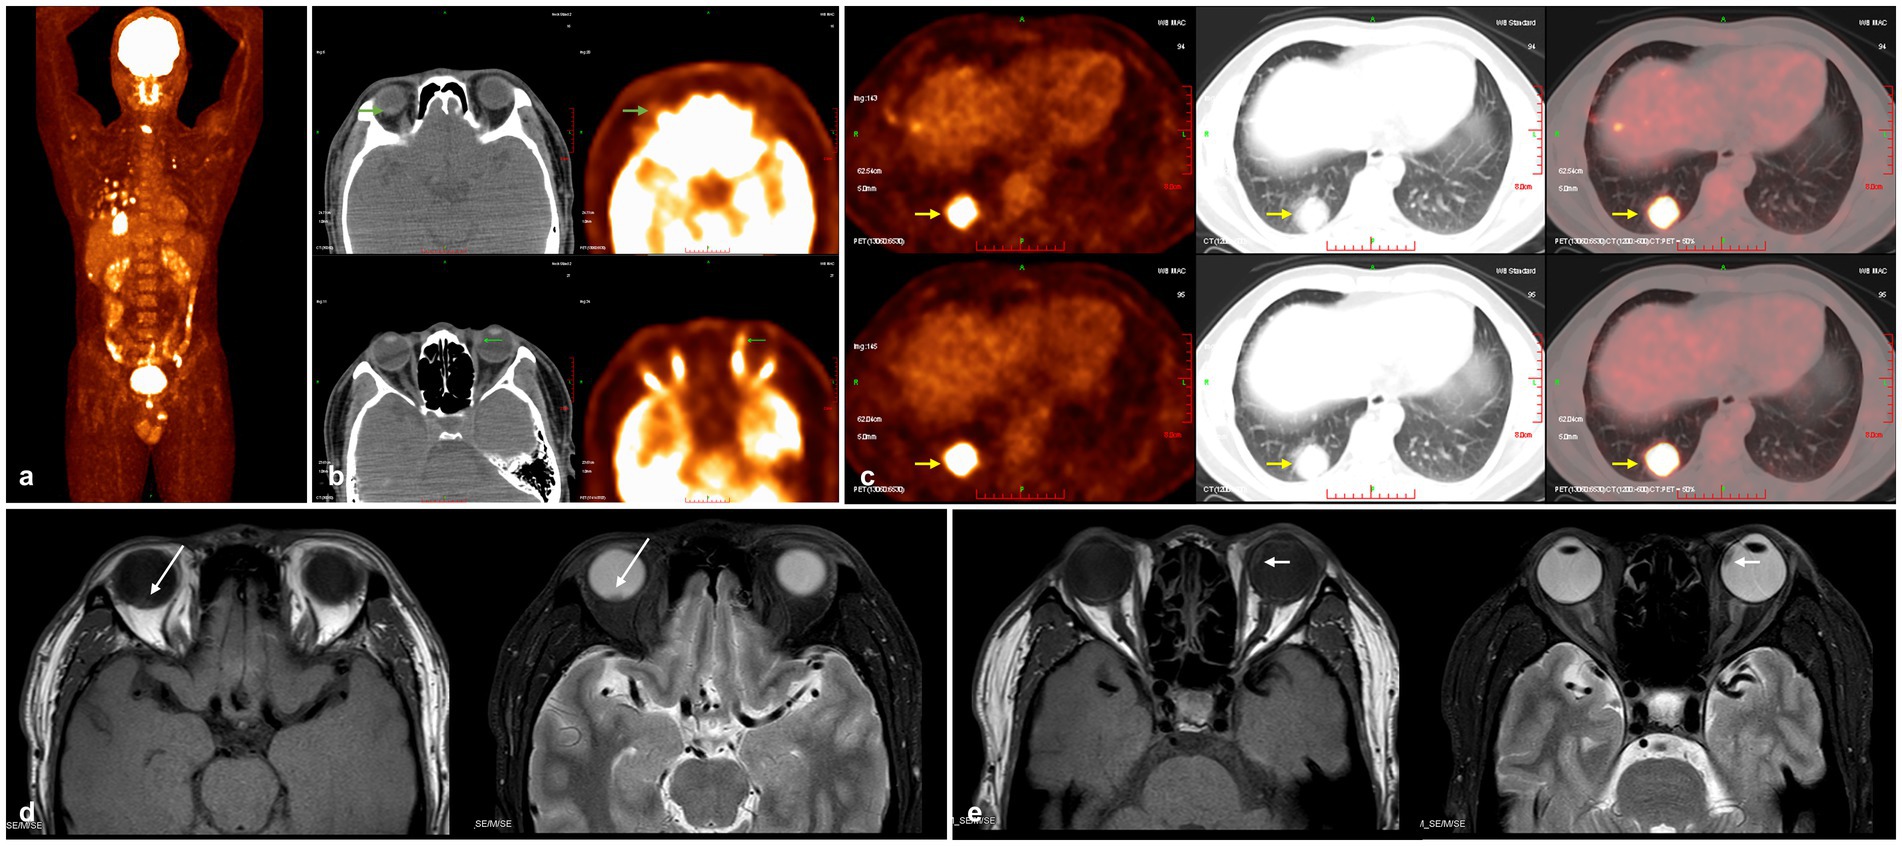

Suspecting uveal metastatic carcinoma, a full-body tumor screening was performed for the patient. Chest computed tomography (CT) revealed multiple nodules and masses of varying sizes in both lungs, with the largest measuring approximately 3.4 × 3.3 cm. Fluorodeoxyglucose positron emission tomography/computed tomography (FDG PET/CT) imaging demonstrated hypermetabolic lesions in the bronchial lymph nodes and bones, alongside the known pulmonary and ocular masses (Figure 2a). The maximum standardized uptake values (SUVmax) for the right and left eye masses were quantified as 2.19 (right eye), 6.69 (left eye), and 13.08 (dominant pulmonary mass) (Figures 2b,c). However, nuclear medicine specialists considered the possibility of primary bilateral choroidal melanoma with pulmonary and skeletal metastasis. The MRI scans demonstrated well-circumscribed intraocular masses with heterogeneous isointensity relative to vitreous on T1-weighted imaging and heterogeneous hypointensity on T2-weighted imaging, observed bilaterally (Figures 2d,e). Following confirmation of adenocarcinoma through percutaneous lung biopsy and a diagnosis of stage 4B lung adenocarcinoma (T4N3M1c), though respiratory specialists recommended excluding primary uveal tumors given the ocular SUVmax fell within the overlap range between metastases and primary melanoma.

Figure 2. Whole-body FDG PET/CT and orbital MRI scans. (a) FDG PET/CT (maximum intensity projection) demonstrates hypermetabolic lesions in bronchial lymph nodes, skeletal system, and lungs. (b) FDG PET/CT shows increased FDG uptake in the masses (green arrow). (c) The largest pulmonary mass is located in the posterior basal segment of the right lower lobe (yellow arrow). (d,e) MRI scans reveal heterogeneous isointense signals in the lesions of both eyes on T1-weighted images, and heterogeneous hypointense signals on T2-weighted images (right eye indicated by a white long arrow, left eye indicated by a white short arrow). FDG PET/CT, fluorodeoxyglucose positron emission tomography/computed tomography; MRI, magnetic resonance imaging.